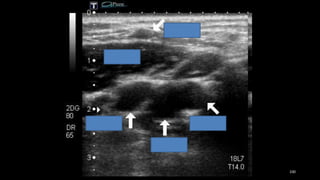

• 1. Imágenes transversales

desde la parte baja del

cuello hacia arriba por

detrás del ángulo de la

mandíbula para localizar la

bifurcación.

Pasos básicos en la exploración.